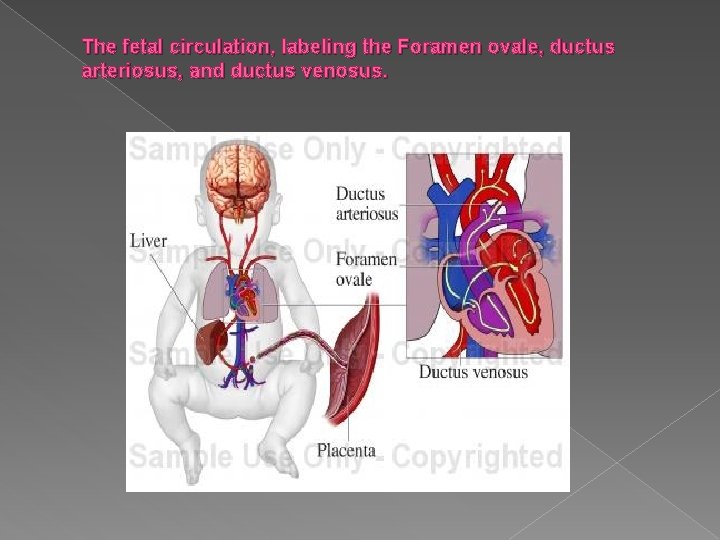

The fetal circulation, labeling the Foramen ovale, ductus arteriosus, and ductus venosus.

� Blood flow through the heart is proportioned as follows: › 60% of right atrial blood passes through the foramen ovale, into the left atrium, and into the systemic circulation. › 40% of right atrial blood enters the right ventricle: � 92% of main pulmonary artery volume bypasses the lungs via the ductus arteriosus and into the system circulation � 8% of the ventricular blood reaches the lungs